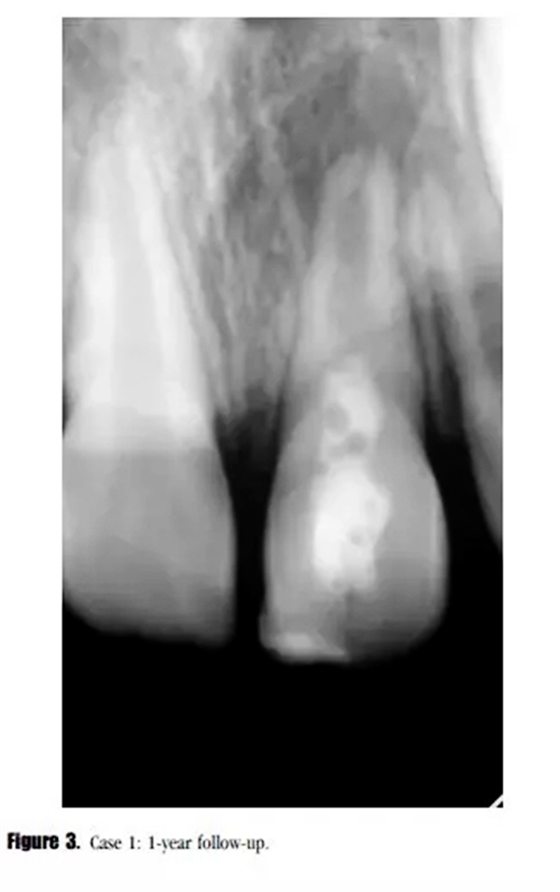

在第12個月的評估中,叩診與捫診又輕微不適。在臨床牙冠上未發(fā)現(xiàn)充填材料與牙體的縫隙以及隱裂線,探診深度正常。我們采用了一種細菌加強型封閉劑來預防再感染。影像學評估顯示,根尖周投射影增大、牙根停止發(fā)育,以及近中根管內(nèi)壁的輕微吸收。(圖3)

診斷為治療后的牙髓疾病復發(fā)。與患者家長商談,1個月后進行常規(guī)根管治療。根管內(nèi)使用 Total Fill RRM ( FKG Dentaire SA , La Chaux-de-Fonds , Switzeland )進行單尖充填(圖4)。